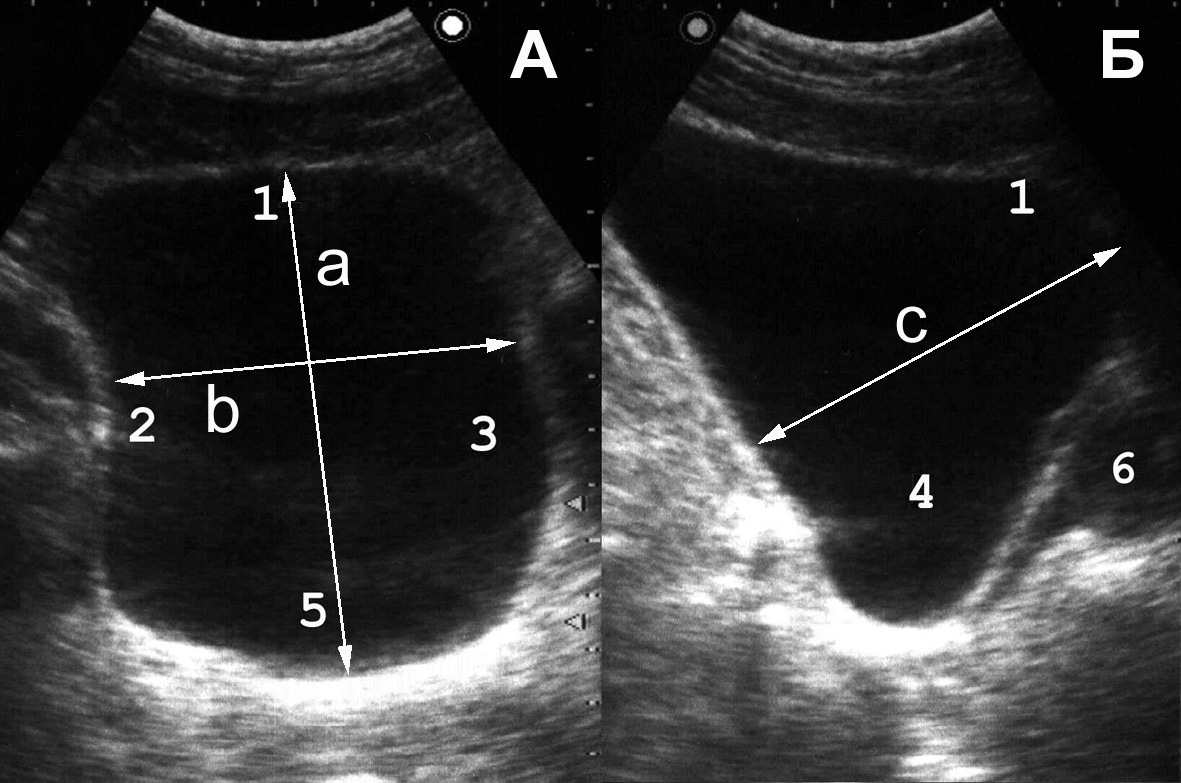

Рис. 4. Сонограмма мочевого пузыря в норме: 1 − мочевой пузырь; 2 − простата; 3 − стенка мочевого пузыря нормальной структуры и толщины. (Продольное сканирование, конвексный датчик 5 МГц, “Logiq-500”).

Рис. 5. При хронической задержке мочи вначале развивается гипертрофия мышечной оболочки мочевого пузыря: 1 − мочевой пузырь; 2 − увеличенная простата; 3 − утолщенная стенка мочевого пузыря. (Продольное сканирование, конвексный датчик 5 МГц, “Logiq-500”).

Рис. 6. В дальнейшем появляется трабекулярность его стенок: 1 − мочевой пузырь; 2 − простата; 3 − стенка пузыря утолщена, с выраженной трабекулярностью. (Продольное сканирование, конвексный датчик 5 МГц, “Logiq-500”).

Рис. 7. В конечной стадии происходит перерастяжение стенок мочевого пузыря: 1 − мочевой пузырь; 2 − простата; 3 − истонченая трабекулярная стенка. (Продольное сканирование, конвексный датчик 5 МГц, “Logiq-500”).

Наиболее часто гипертрофия стенок связана с нарушением оттока мочи вследствие инфравезикальной обструкции. Ее причинами могут быть доброкачественная гиперплазия или рак предстательной железы, функциональный или органический стеноз шейки мочевого пузыря (болезнь Мариона), стриктура уретры. При прогрессировании заболевания и увеличении объема остаточной мочи утолщение мышечных пучков становится неравномерным, внутренняя поверхность мочевого пузыря принимает трабекулярный вид (рис. 6). Длительное существование хронической задержки мочи приводит к дальнейшему истончению стенок пузыря (рис. 7). Объем остаточной мочи может при этом достигать 1 л и более.